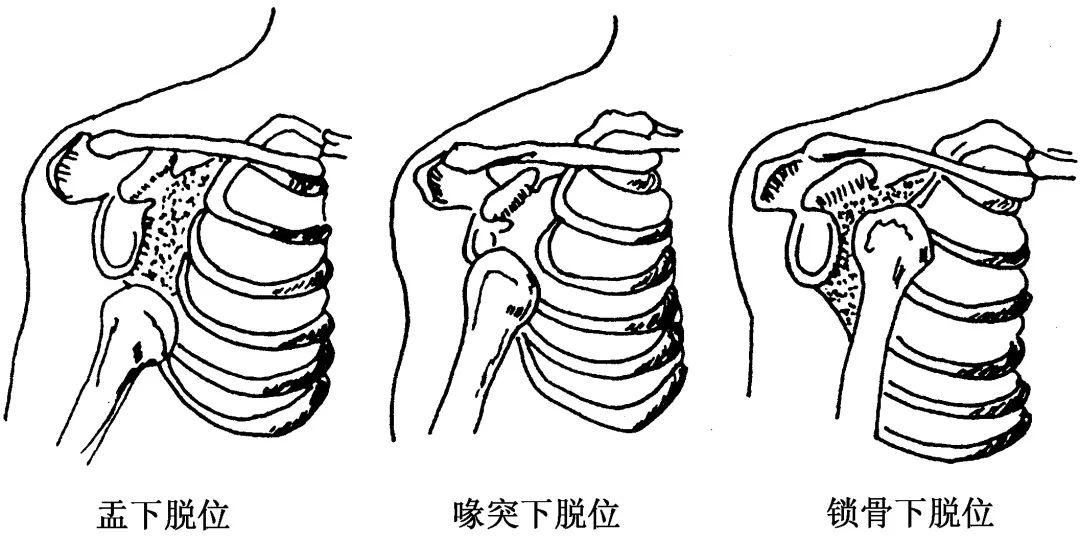

外伤,明显的外伤引起肩关节脱位、骨折等,一般较易诊断。